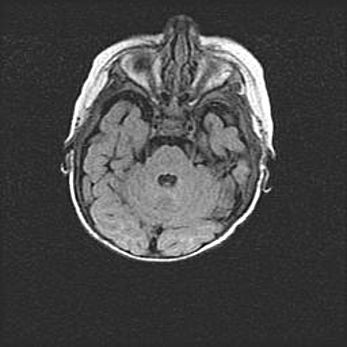

Наружная гидроцефалия с возможной атрофией височных областей.

Возраст: 28 дней

Вес: 3670 г

Пол: мужской

Окружность головы: 38 см

Срок гестации: 40 недель

Гидроцефалия головного мозга у новорожденных – это заболевание, которое характеризуется скоплением избыточного количества спинномозговой жидкости в желудочковой системе головного мозга в результате затруднения её перемещения от места выработки к месту поглощения в кровеносную систему или вследствие нарушения абсорбции. При открытой наружной форме гидроцефалии у новорожденных расширяются и переполняются субарахноидные пространства.

При нормотензивных  формах,  которые,  как  правило,  являются  следствием  перенесенных ишемических  повреждений  паренхимы  мозга,  возможно  сочетание микроцефалии  с нормотензивной гидроцефалией. В основе данных изменений лежит атрофия больших полушарий с преимущественной  локализацией  в  лобно-височных  областях.